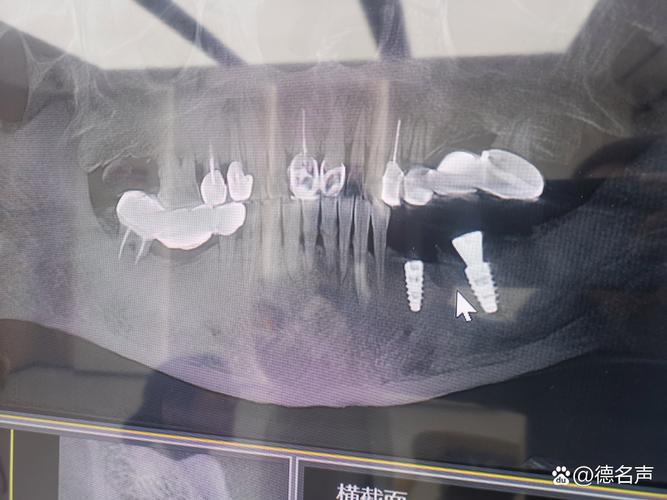

(图片来源网络,侵删)